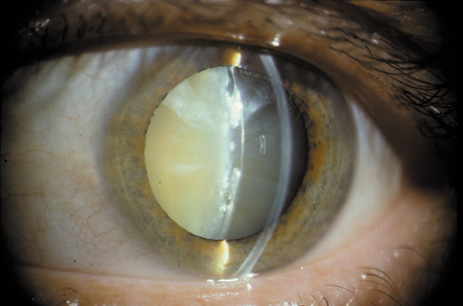

Nuclear cataracts tend to progress slowly. The refractive index of the lens changes as the nucleus progressively hardens, which usually results in increasing myopia.20,21 In some patients this is accompanied by optical distortion, especially of distant images, while near vision remains unaffected. A nuclear cataract is best seen with the narrow-beam direct illumination employed by the slit-lamp, which reveals the color and generalized haze or opalescence of the nucleus. In the early stages, the two halves (cotyledons) of the embryonic nucleus remain visible (Fig. 3). Later the entire nucleus appears as a homogeneous mass in contrast to the cortex (Fig. 4). Retroillumination may show the “oil droplet” effect (Fig. 5). Sometimes one may notice crystals in the lens nucleus (known as a Christmas tree cataract; Fig. 6A and B).

Fig. 3. Early nuclear cataract. Note the “cotyledons” in the nucleus.

Fig. 4. Advanced nuclear cataract. Note the homogeneous nuclear opacity.